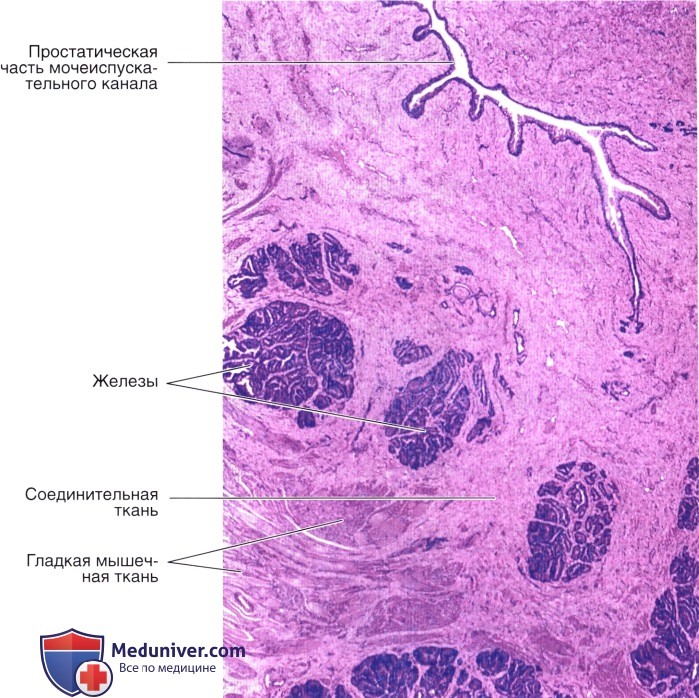

Простата, обычно ассоциируемая с мужским здоровьем после полового созревания, также присутствует у детей, хотя и в значительно меньших размерах. Этот орган, расположенный под мочевым пузырем и окружающий уретру, играет роль в выработке жидкости, которая составляет часть семенной жидкости. Несмотря на то, что проблемы с простатой у детей встречаются редко, понимание её развития и потенциальных патологий важно для ранней диагностики и лечения.